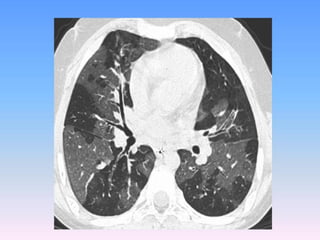

Common CT findings include bronchial wall

thickening, air trapping, and bronchiectasis.

Automated techniques are now

being used to evaluate the extent of airway wall

thickening in a highly objective and reproducible

manner. Multiple studies have demonstrated that

disease severity correlates with the degree of

bronchial thickening and air trapping.